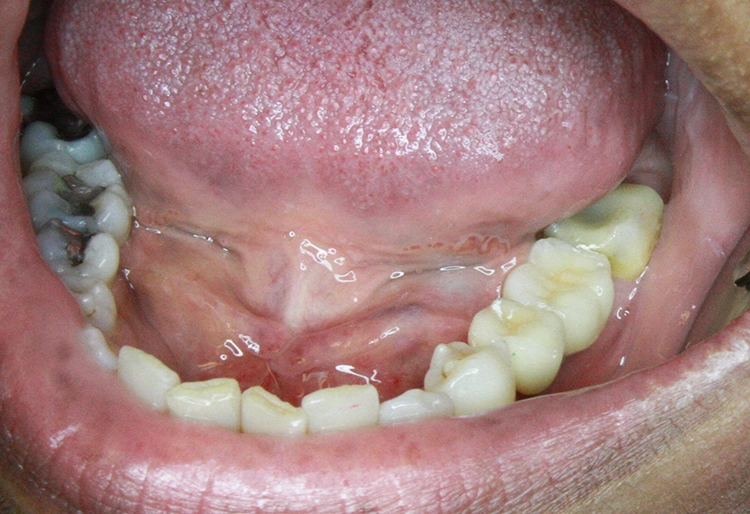

Nach iatrogener Periostablösung ist eine Mangelernährung des Knochens, auch Jahre später, sehr wahrscheinlich – mit der Folge einer iatrogenen Knochenresorption. Auch im Zuge einer klassisch-prothetischen „Implantat-Wiedereröffnung“ mit „kleinem Lappen“ wird das periimplantäre Periost unnötig verletzt.

Das MIMI-Insertionsprotokoll unterscheidet sich aber noch in weiteren Punkten von einer reinen „Flapless“ (lappenlos)-Technik. Denn MIMI-Indikationen gehen über das lappenlose Implantieren in „breite Kiefer“ und deren prothetische Versorgung hinaus.